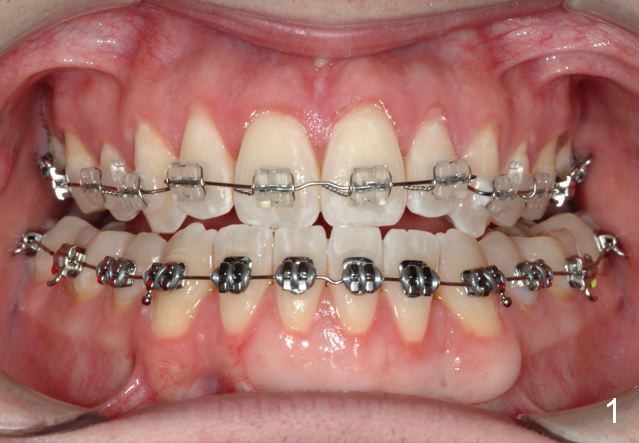

Initial bonding on 08/04/2014 (Fig.1-3); follow up appointments (09/20/2014 (Fig.4,5); 11/11/2014 (Fig.6,7), prepared for maxillary segmental surgery to expand, advance, and level.

I routinely start off with a round NiTi AW, like .014 in the .018 slot, then to .016 and up to 16X22 NiTi. Then I go to rectangular SS.  I segmented the AW to facilitate the surgery.

Thanks.  It is my understanding that preop ortho is to decompensate, in your case, make anterior cross bite worse so that there is more room to correct the cross bite.  In fact the lower continuous AW does work toward my dream goal.  How to correct proclined upper anteriors?

Your understanding is spot on!